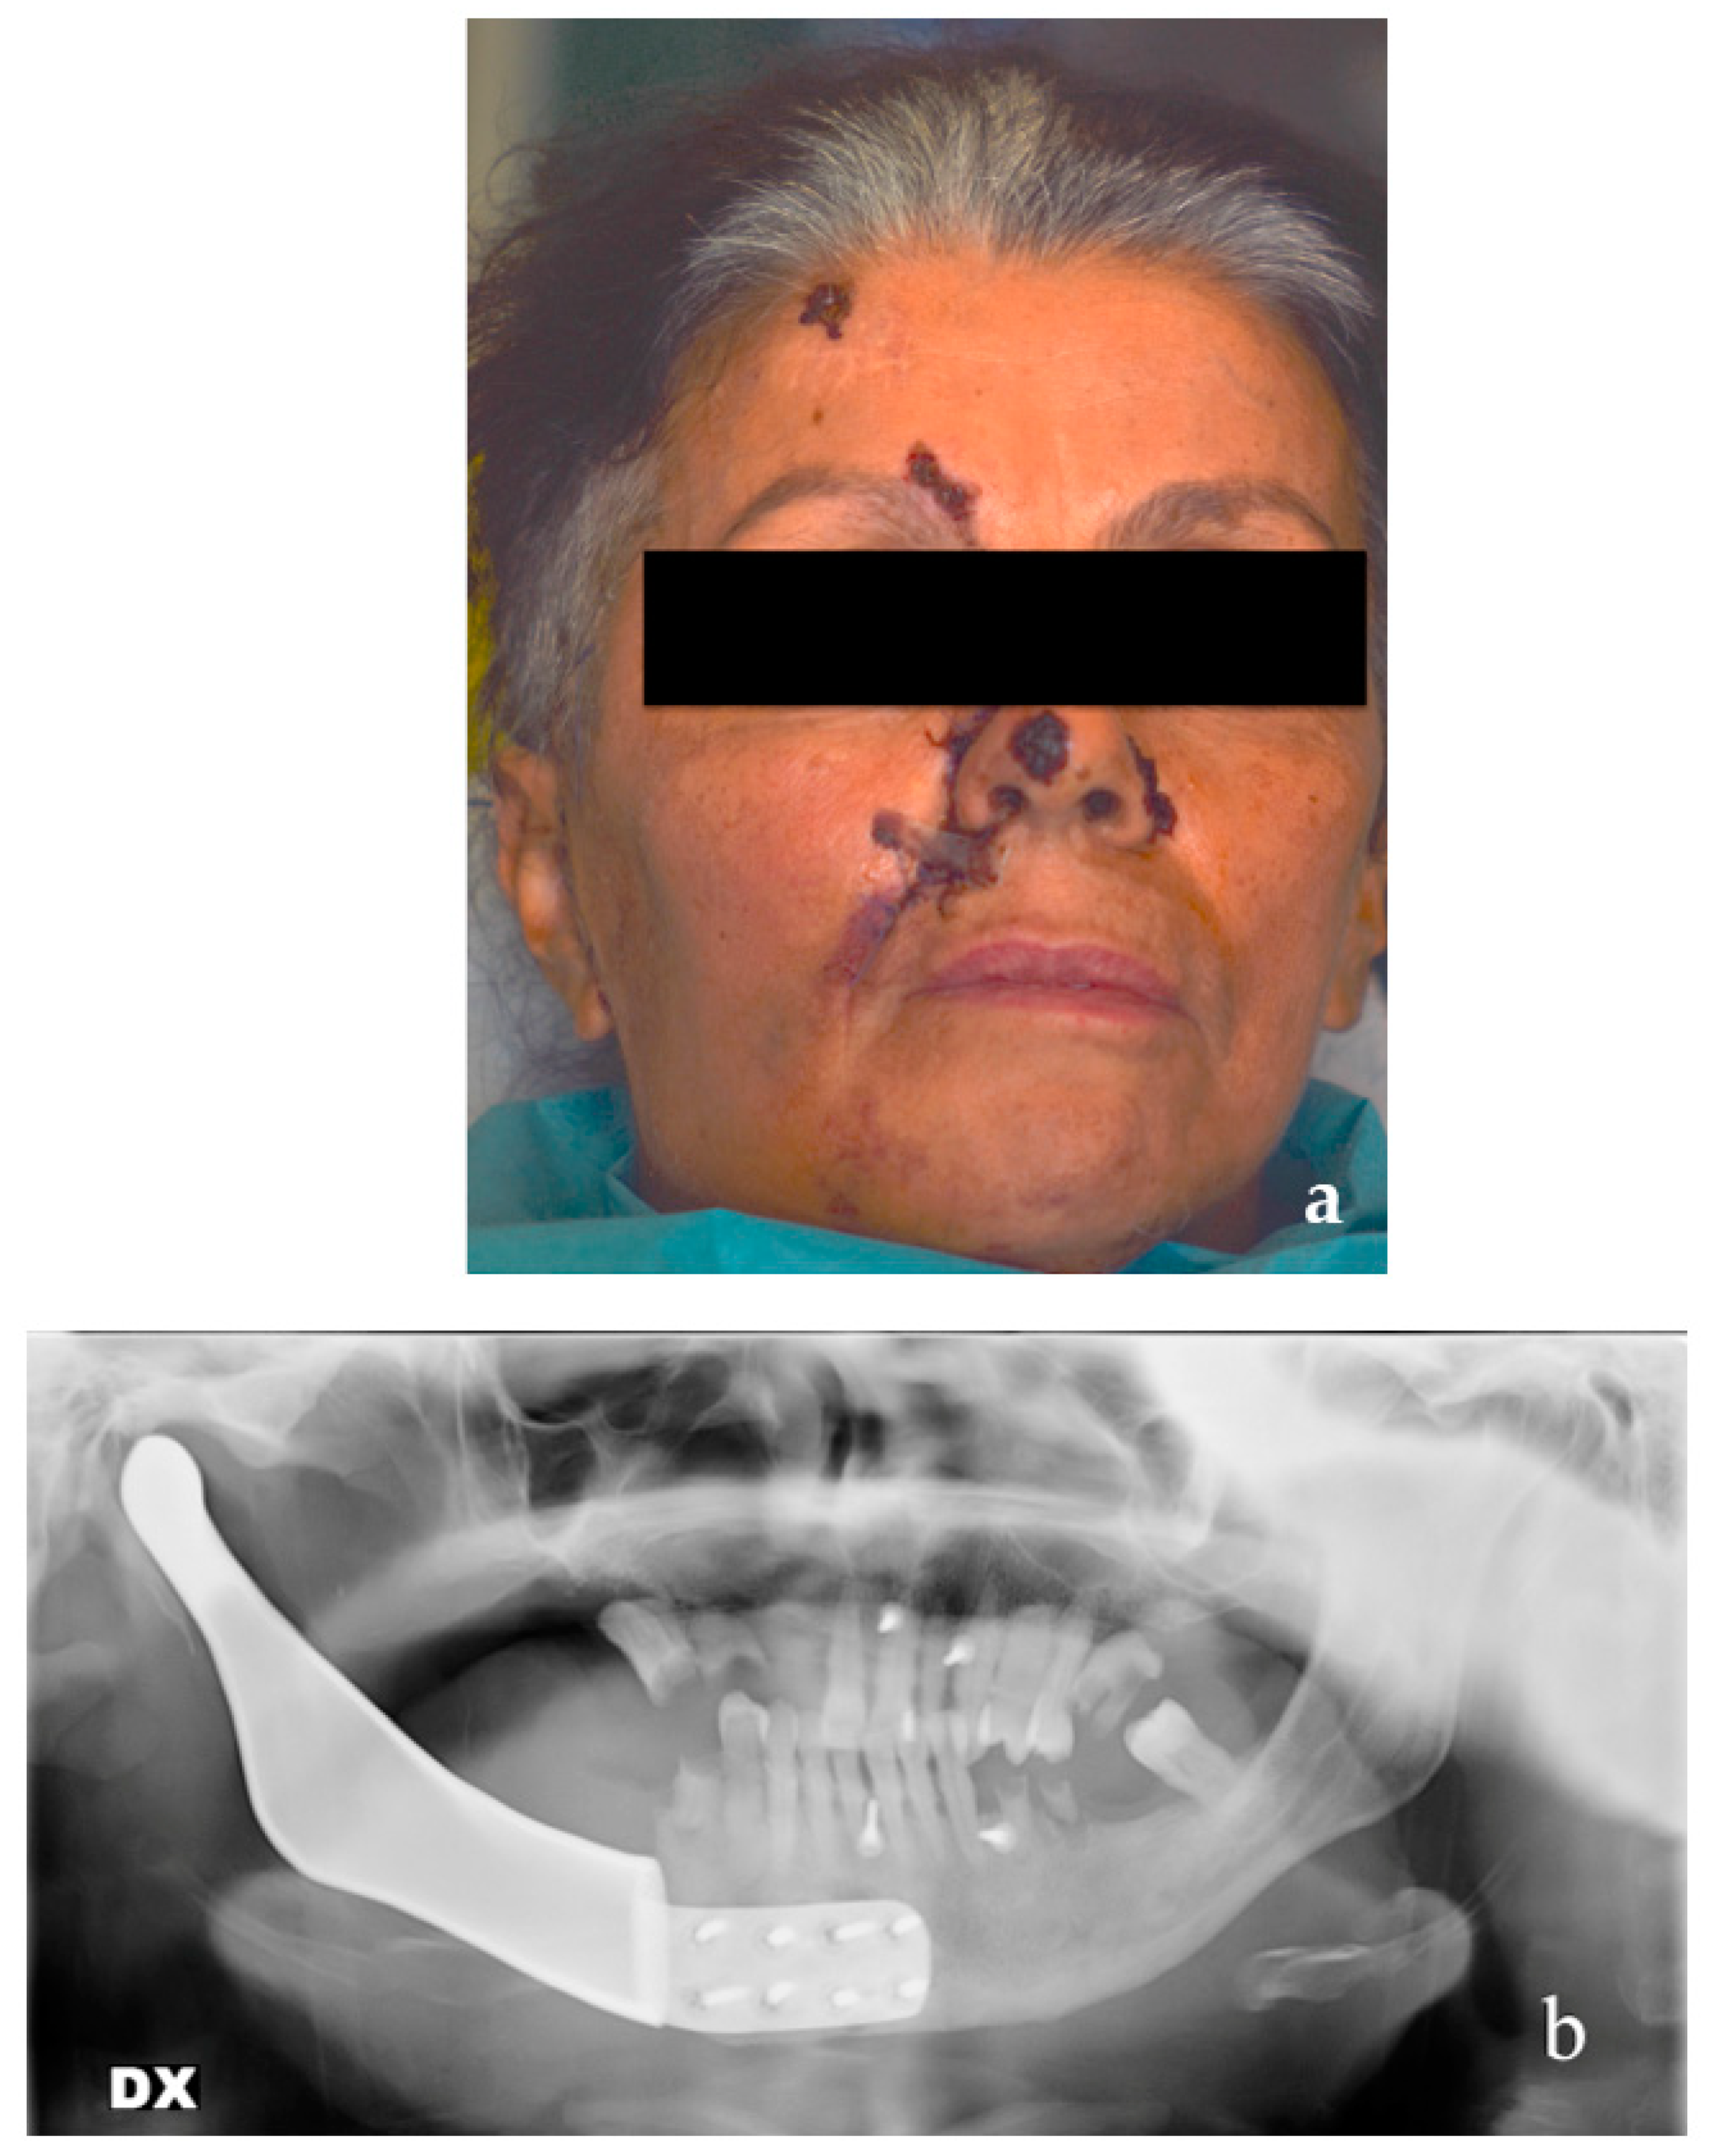

2.6. Patient #2

2.8. Surgical Sequence Case #2